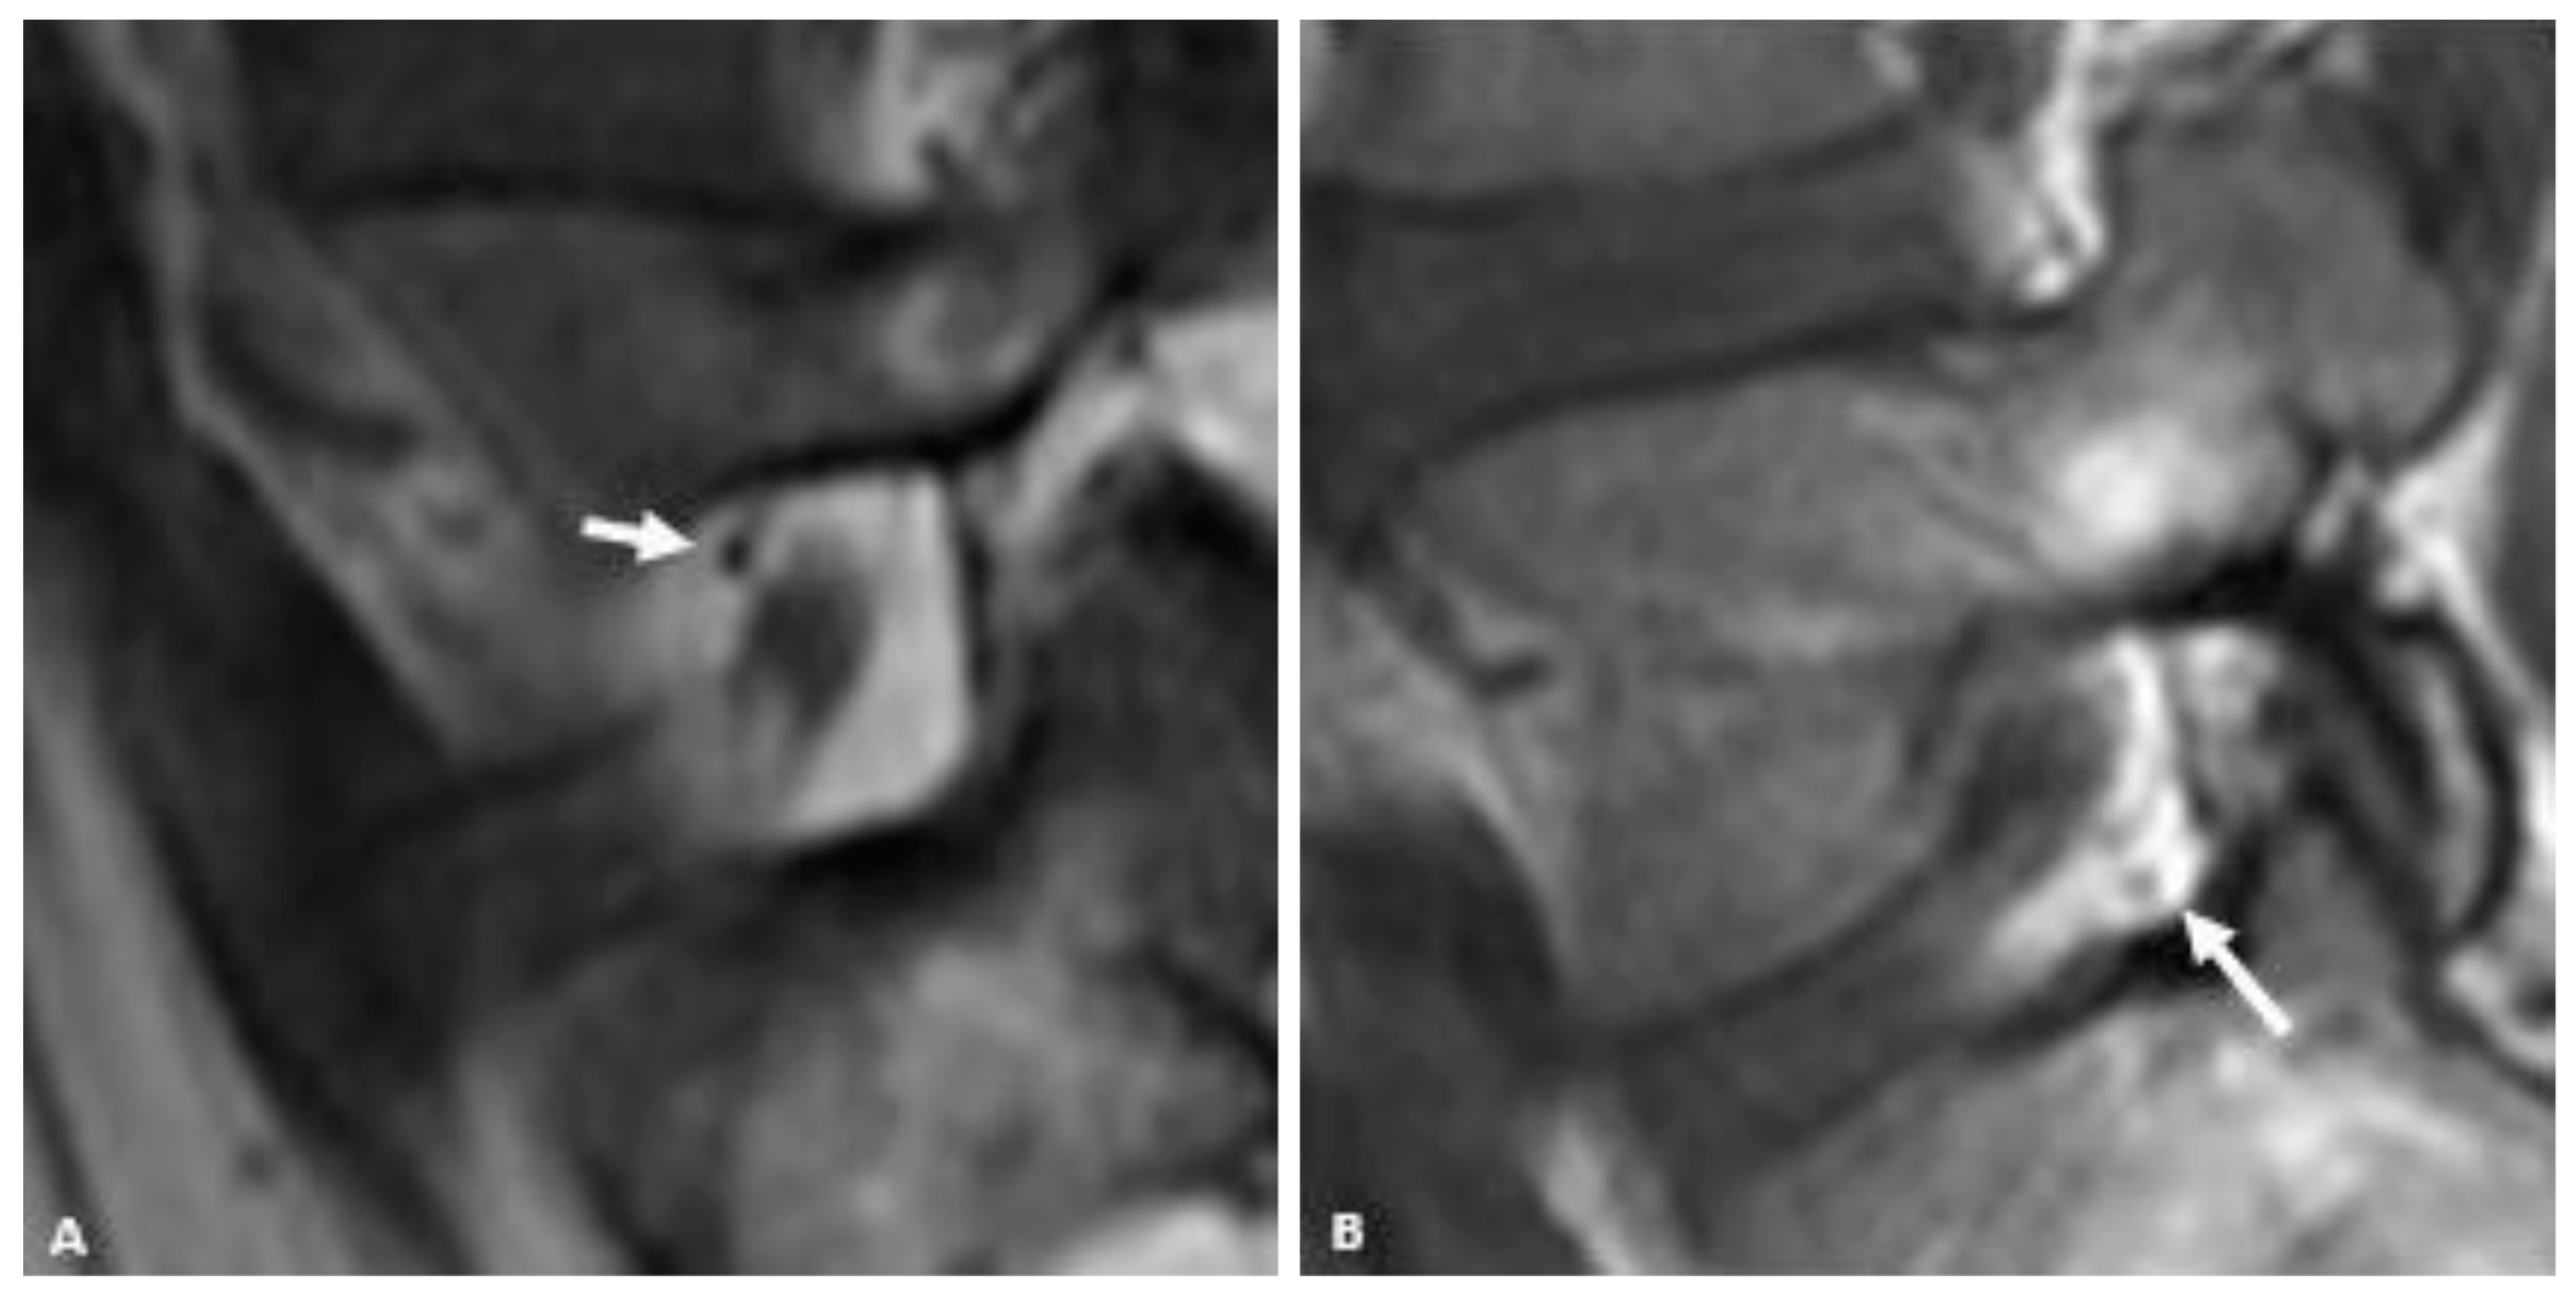

For qualitatively determining the presence and location of vessels within the neural foramen, the reviewers were instructed to use the same MRI slice that they used to judge the foraminal fat. A convincing punctate low signal intensity structure next to the nerve root (either antero-superiorly or postero-inferiorly) on the sagittal T1 sequence was considered a vessel (Figure 2). Vessels were considered present when seen but considered “Not Applicable” when not seen because in cases where there was no fat (“None”) in the neural foramen, it would not be possible to see a vessel, and because many vessels may be too small to see within the resolution limits of the MRI.

Figure 2.

Representative sagittal T1w MR images of the L5-S1 neural foramen demonstrating foraminal vessels (arrows) in the antero-superior foramen (A) and postero-inferior foramen (B).